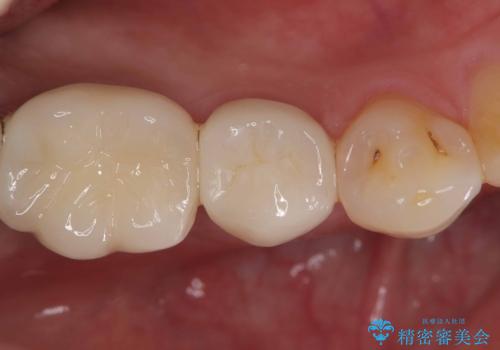

その後、新しい土台を立て、仮歯に置き換えたのち、フルジルコニアクラウンにて治療を行いました。

患者さんからは、「とてもお口に馴染んで気に入っている」とおっしゃって頂けました。

費用:仮歯1万円、フルジルコニアクラウン7万円(税別)